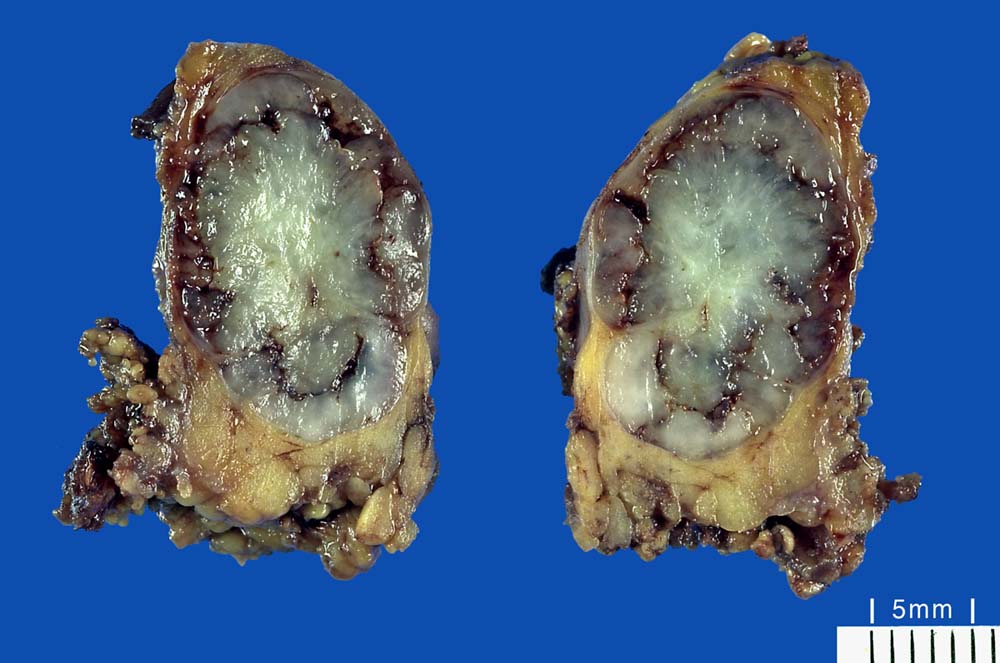

PathoPic ID 9389 - Pleomorphes Adenom der Speicheldrüse

Pleomorphes Adenom der Speicheldrüse

benigner Tumor

Speicheldrüse

Kopf & Hals, Sinnesorgane

Grauweisser glasiger Knoten im lobulierten ockerfarbenen Speicheldrüsenparenchym.

Parotistumor

Makroskopie